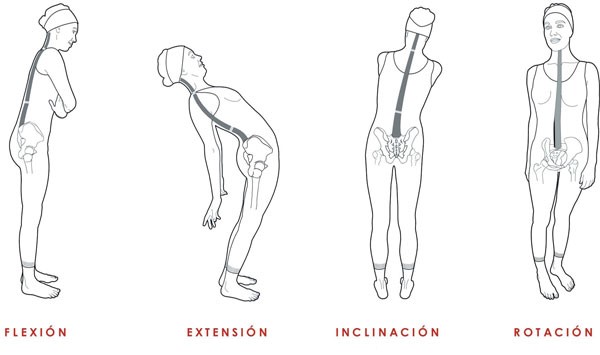

La columna vertebral puede realizar cinco movimientos:

A. Flexión

B. Extensión

C. Inclinación lateral

D. Rotación